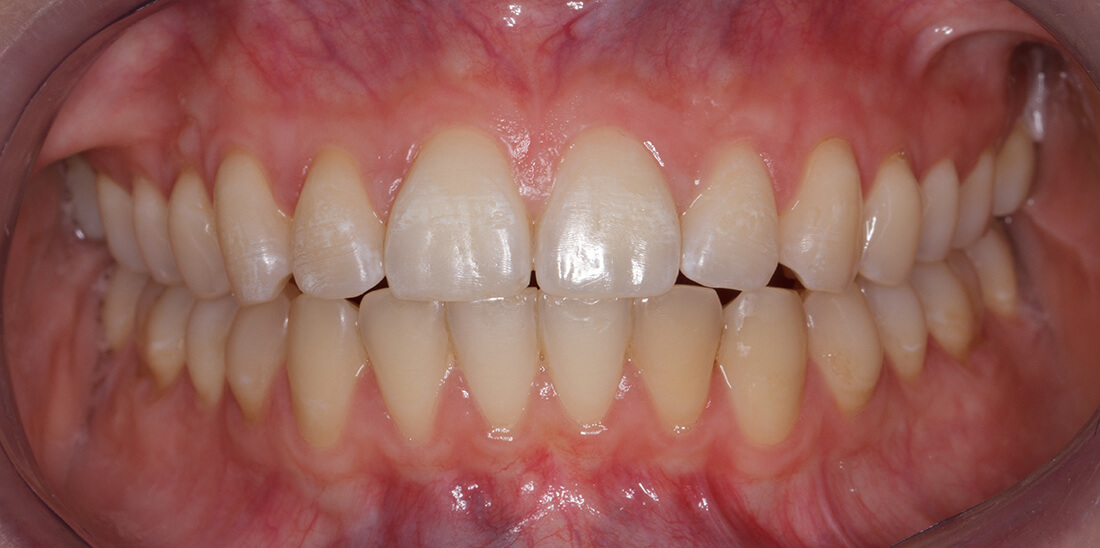

La malattia parodontale

La malattia parodontale è molto diffusa nella popolazione con segni e sintomi che possono variare da persona a persona. Vi sono forme giovanili che colpiscono la fascia di età 18-30 anni ma solitamente sono interessate le persone con più di 35 anni. La Parodontite è la causa principale della perdita di denti negli adulti.

Solitamente è scarsamente curata e percepita dal paziente. Il motivo è dato dal fatto che nelle fasi iniziali della malattia non si riscontra quasi mai dolore o altri disturbi che spingono il paziente a recarsi presso un centro odontoiatrico per effettuare un controllo.

Parodontite (piorrea)

La parodontite, più conosciuta con il nome di piorrea, è una malattia che nello stadio iniziale coinvolge i tessuti intorno alla radice del dente e dell’osso fino a provocare una mobilità del dente stesso, la formazione di tasche e la perdita dell’elemento dentale.

Sintomi

Anche se, come detto in precedenza, la malattia parodontale solitamente non provoca dolore, i segnenti sintomi dovrebbero essere considerati un campanello d’allarme: sanguinamento delle gengive, mobilità dentale, dolore durante lo spazzolamento, alito cattivo.